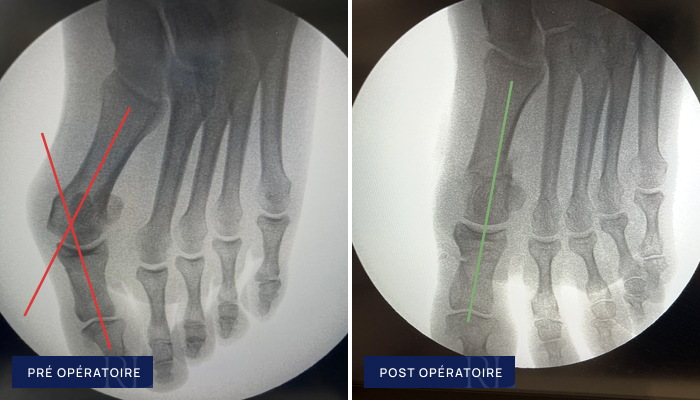

Radiographies pré et post opératoire d’Hallux Valgus

À gauche : Déformation du gros orteil (hallux valgus du pied)

À droite : Correction mini invasive (ostéotomies percutanées)